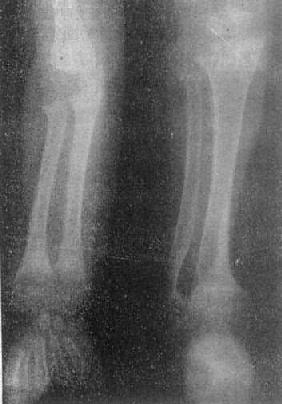

图2-1-8 前臂及小腿骨骨质软化—佝偻病骨质普遍密度减低,骨皮质薄,边缘不清,骨小梁

模糊,骨变弯、变形。干骺端宽大呈杯口状变形,骺与干骺干骺端距离增宽。骺边缘模糊。腕骨出现少

骨质软化的X线表现主要是由于骨内钙盐减少而引起的骨密度减低,以腰椎和骨盆为明显。与骨质疏松不同的是骨小梁和骨皮质边缘模糊,系因骨组织内含有大量未经钙化的骨样组织所致(图2-1-8)。由于骨质软化,承重骨骼常发生各种变形(图2-1-9)。此外,还可见假骨折线,表现为宽约1~2mm的光滑透明线,与骨皮质垂直,边缘稍致密,好发于耻骨支、肱骨、股骨上段和胫骨等。